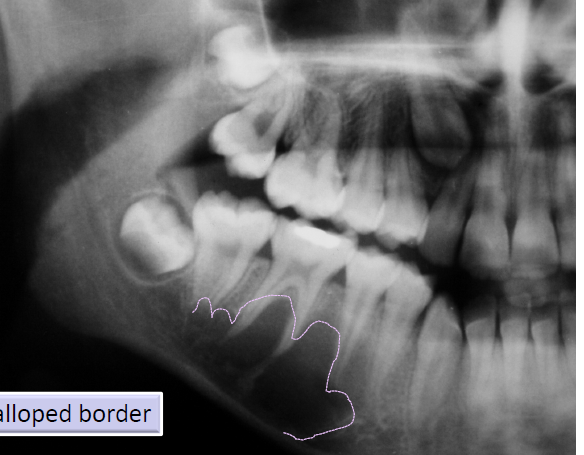

aneurysmal bone cyst

not a true cyst, caused by increased venous pressure with resultant dilation and rupture of the local vascular network

“blood soaked sponge” as surgical finding

arising in a pre-existing bone lesion

may cause pain and swelling

large unilocular or multilocular radiolucency